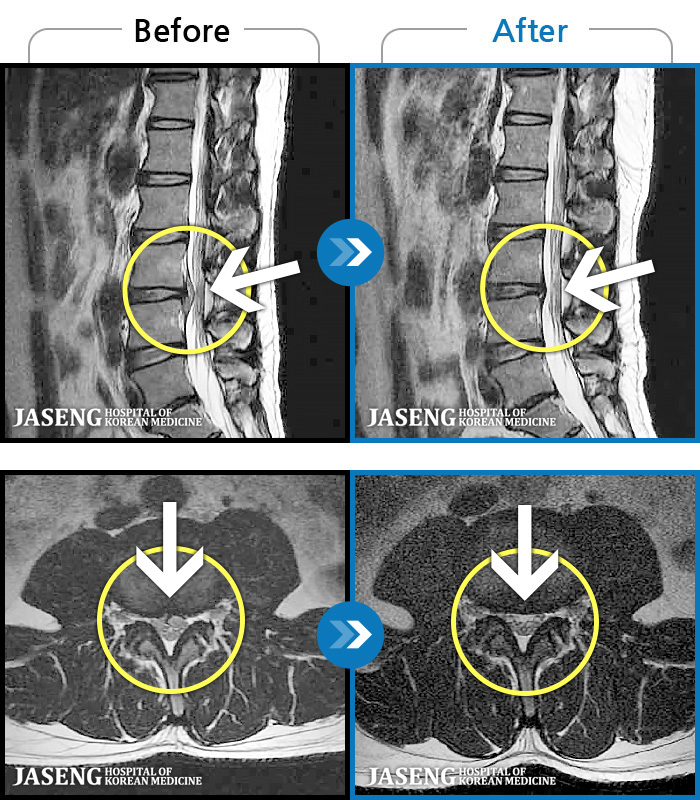

123 MRI ũ ʸ Ȯϼ.

[뱸] 19.11.28~25.05.06